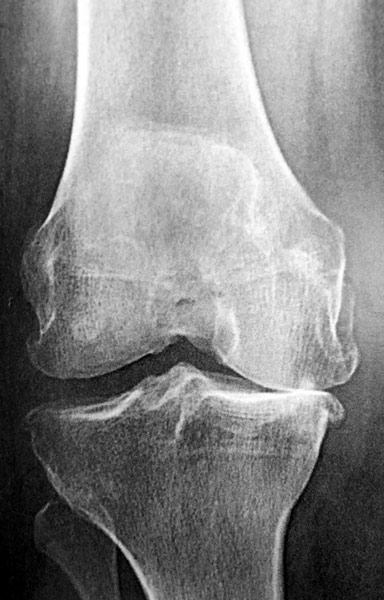

L’arthrose du genou est extrêmement répandue dans la population : elle touche 30% des gens âgés de plus de 60 ans, en majorité des femmes.

L’arthrose est liée à la dégénérescence progressive du cartilage. Lorsque le cartilage est détruit, l’os frotte contre l’os, ce qui engendre des douleurs, une boiterie, une limitation du périmètre de marche et un handicap important dans la vie de tous les jours.

Arthrose des trois compartiments du genou (tri-compartimentale).

Douleur + raideur + boiterie. Homme 75 ans, opéré du ligament croisé antérieur 40 ans auparavant. On propose une prothèse totale du genou. Rééducation immédiate, récupération en 4 mois sauf complication.